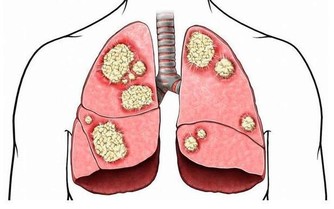

實際上,目前我們已經發現了數百種癌症,每個都具有獨特的分子特徵和可變的臨床表達。比如,在神經腫瘤學中,已經確定了至少120種腦和脊髓癌亞型。對於這種多樣化的敵人,我們的診斷和治療方法必須擴大,也必然很難。

儘管人類在數十年的研究中投入了大量資金,但許多人認為癌症是無法治癒的。但是,雖然癌症可能是一種毀滅性的診斷,但並非沒有希望。免疫療法的新研究,給我們帶來了新的希望,甚至可能完全擊敗它。